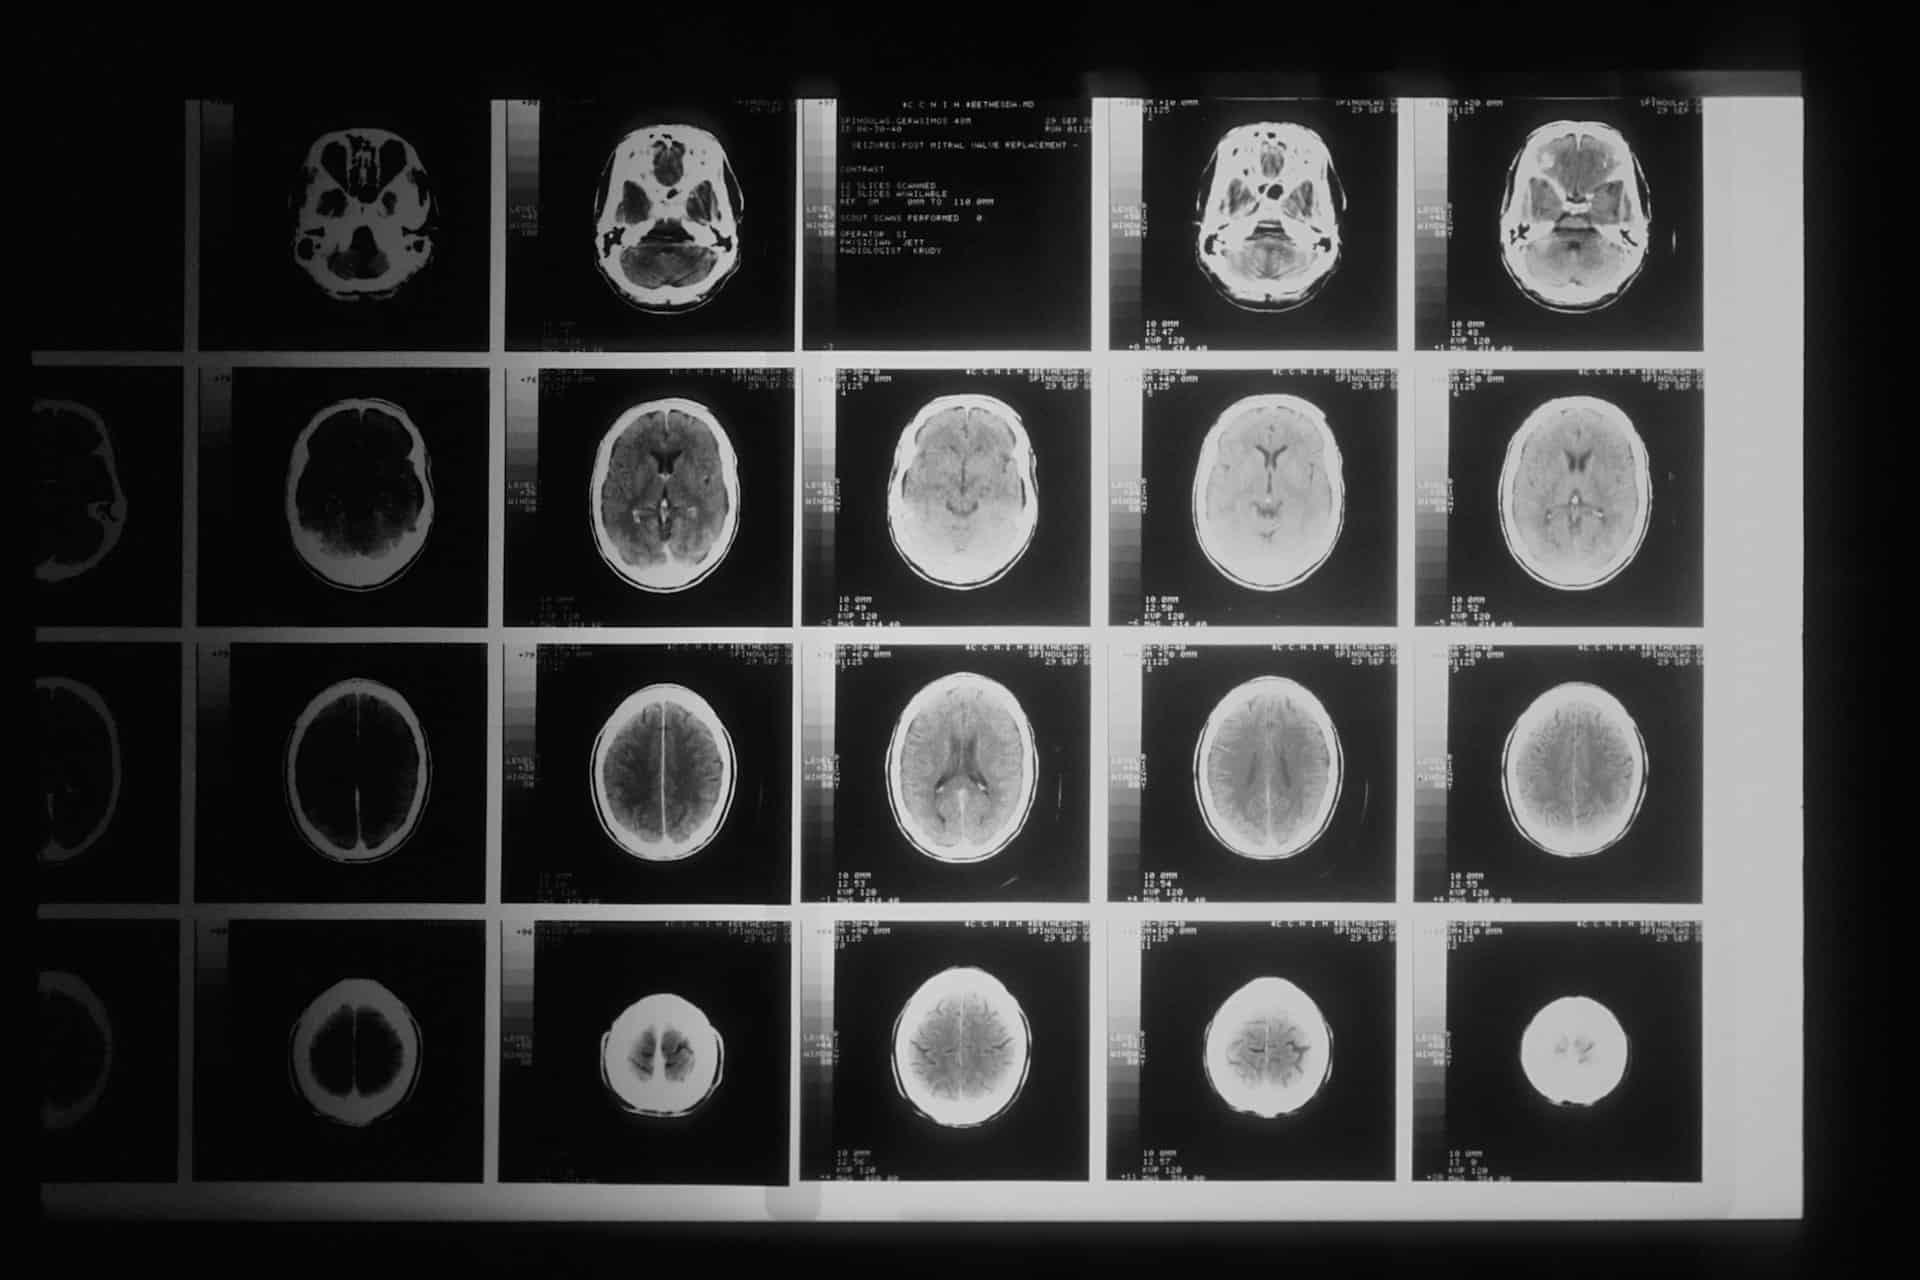

Diagnosing a TBI can be difficult. While magnetic resonance imaging (MRI) and computed tomography (CT) scans can be used, some research suggests that single photon emission computed tomography (SPECT) scans are also useful. This article examines the different methods for diagnosing a TBI and why this may matter in a legal case.

Sometimes MRI or CT scans, the most common tools for diagnosing brain injuries, do not demonstrate anatomic abnormalities consistent with a TBI diagnosis.

Some specialist physicians have turned to SPECT scans in an attempt to diagnose mild TBIs. Using a radioactive tracer and CT scan, a SPECT scan can show blood flow through organs, such as the brain. This may identify a lack of blood flow to an injured area.